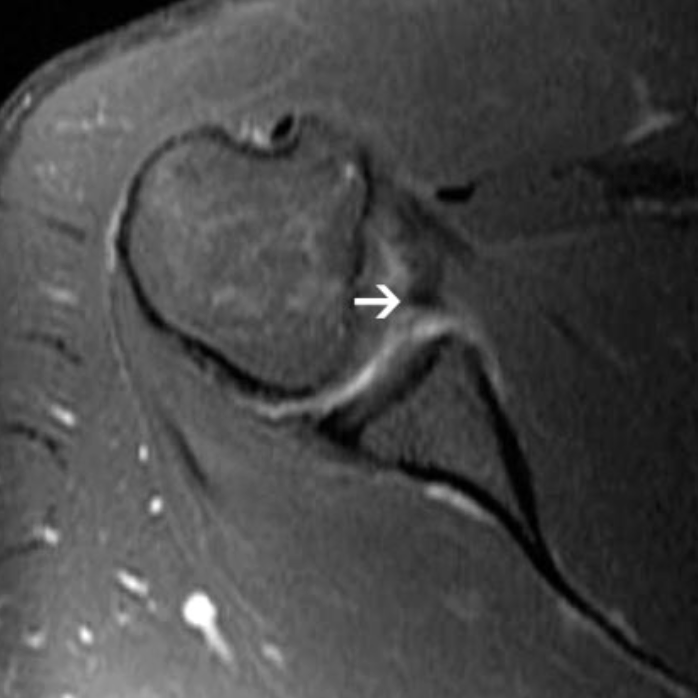

A shoulder labral tear is an injury to the ring of cartilage (labrum) that helps keep your shoulder joint stable. The labrum acts like a bumper, deepening the socket where your arm bone fits and helping keep your shoulder from slipping out of place. Labral tears often happen after a fall, sports injury, or sudden force to the shoulder, and can lead to pain, clicking, or a feeling that the shoulder might "pop out" or dislocate.[12]

• Certain types of labral tears (like ALPSA lesions or tears in the lower front part of the labrum)